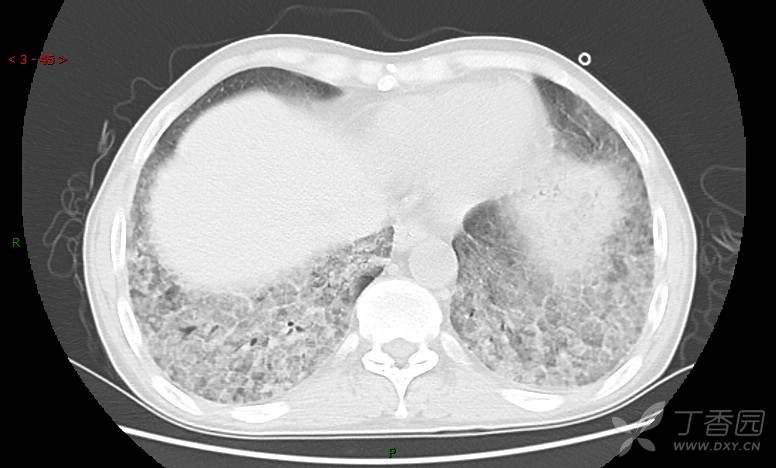

地图+铺路石征=PAP?那升高的CEA怎么说(病例3连发,附其他2例链接)

患者男,42岁,咳嗽半年余,加重伴憋喘2月余。

患者半年余前无明显诱因出现间断咳嗽,干咳为主,偶咳少量黄白痰,剧烈咳嗽或运动后可出现轻度憋喘,无高热、脓臭痰,无胸痛、咯血及晕厥,无低热乏力及盗汗,无心前区压榨感及夜间阵发性呼吸困难,初未在意,未予正规诊治。2月余前患者自觉上述症状较前加重,咳嗽、憋喘明显,黄白色粘痰略有增多,伴有发热,热前伴有畏寒、寒战,体温最高达38.9℃,先后就诊多家医院,入住重症监护室,未行气管插管,考虑“重症肺炎”,给予“美罗培南、复方磺胺甲噁唑”等药物抗感染,“卡泊芬净”抗真菌,并给予“甲泼尼龙”等药物治疗35天,经治疗后症状好转于2018-04-02出院。患者自出院后仅应用中药治疗(具体不详),并给予家庭氧疗,平素仍有间断咳嗽,咳少量黄白色粘痰,活动后憋喘明显,活动耐量差,以卧床为主。